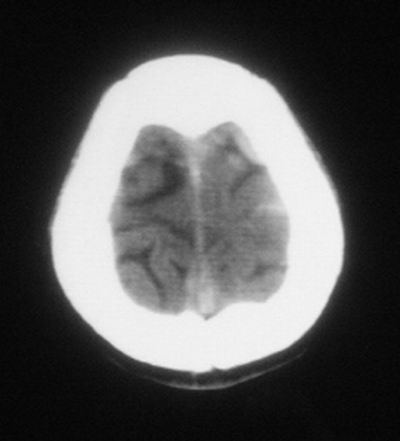

患者,男,30岁,右侧面部麻木,右上肢活动受限27小时。pe:神清、呼吸平稳,口角左歪,右上肢活动受限,右手掌握力消失,右侧躯体痛觉减退。

第一次颅脑ct扫描:左侧额顶叶血肿。